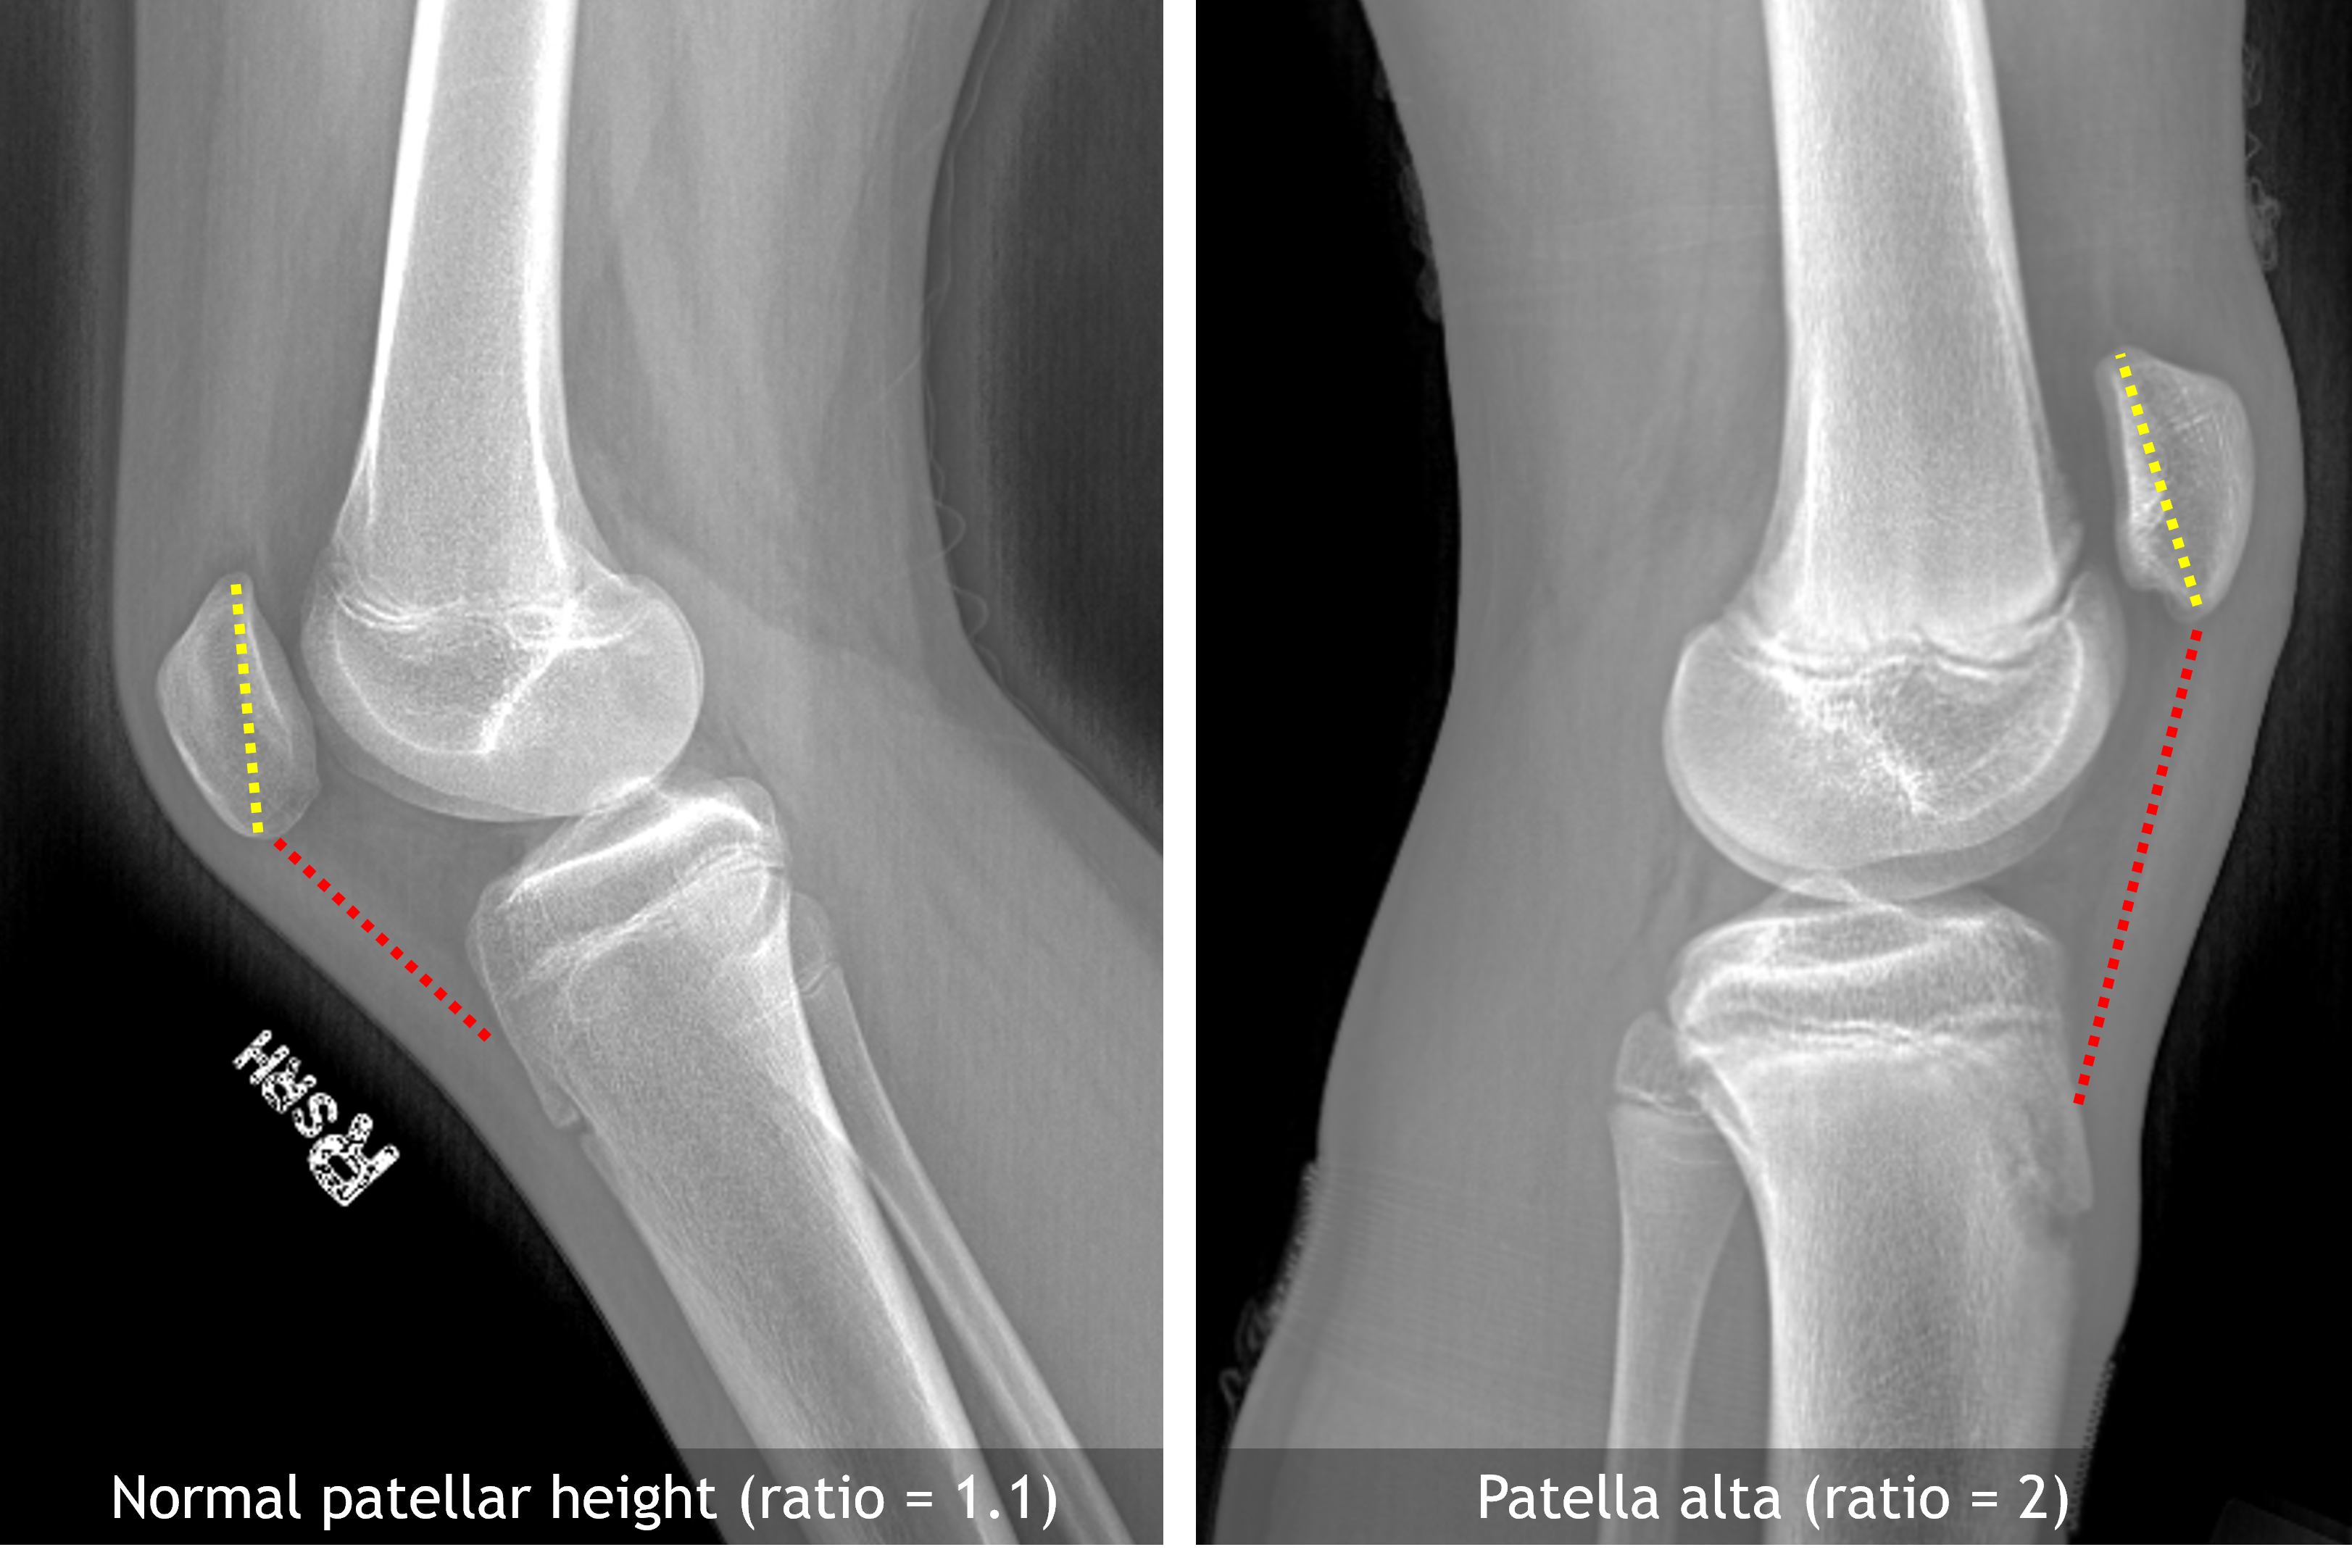

Sample ReportNo acute fracture or joint effusion.

Patella alta. This finding is age-indeterminate and can be further evaluated with MRI if there is ongoing clinical concern.